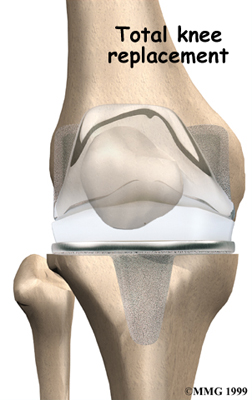

Artificial Knee Replacement

An artificial knee replacement is the ultimate solution for advanced knee OA.

Surgeons prefer not to put a new knee joint in patients younger than 60. This is because younger patients are generally more active and might put too much stress on the joint, causing it to loosen or even crack. A revision surgery to replace a damaged prosthesis is harder to do, has more possible complications, and is usually less successful than a first-time joint replacement surgery.

Related Document: FYZICAL McKinney Coit's Guide to Artificial Joint Replacement of the Knee